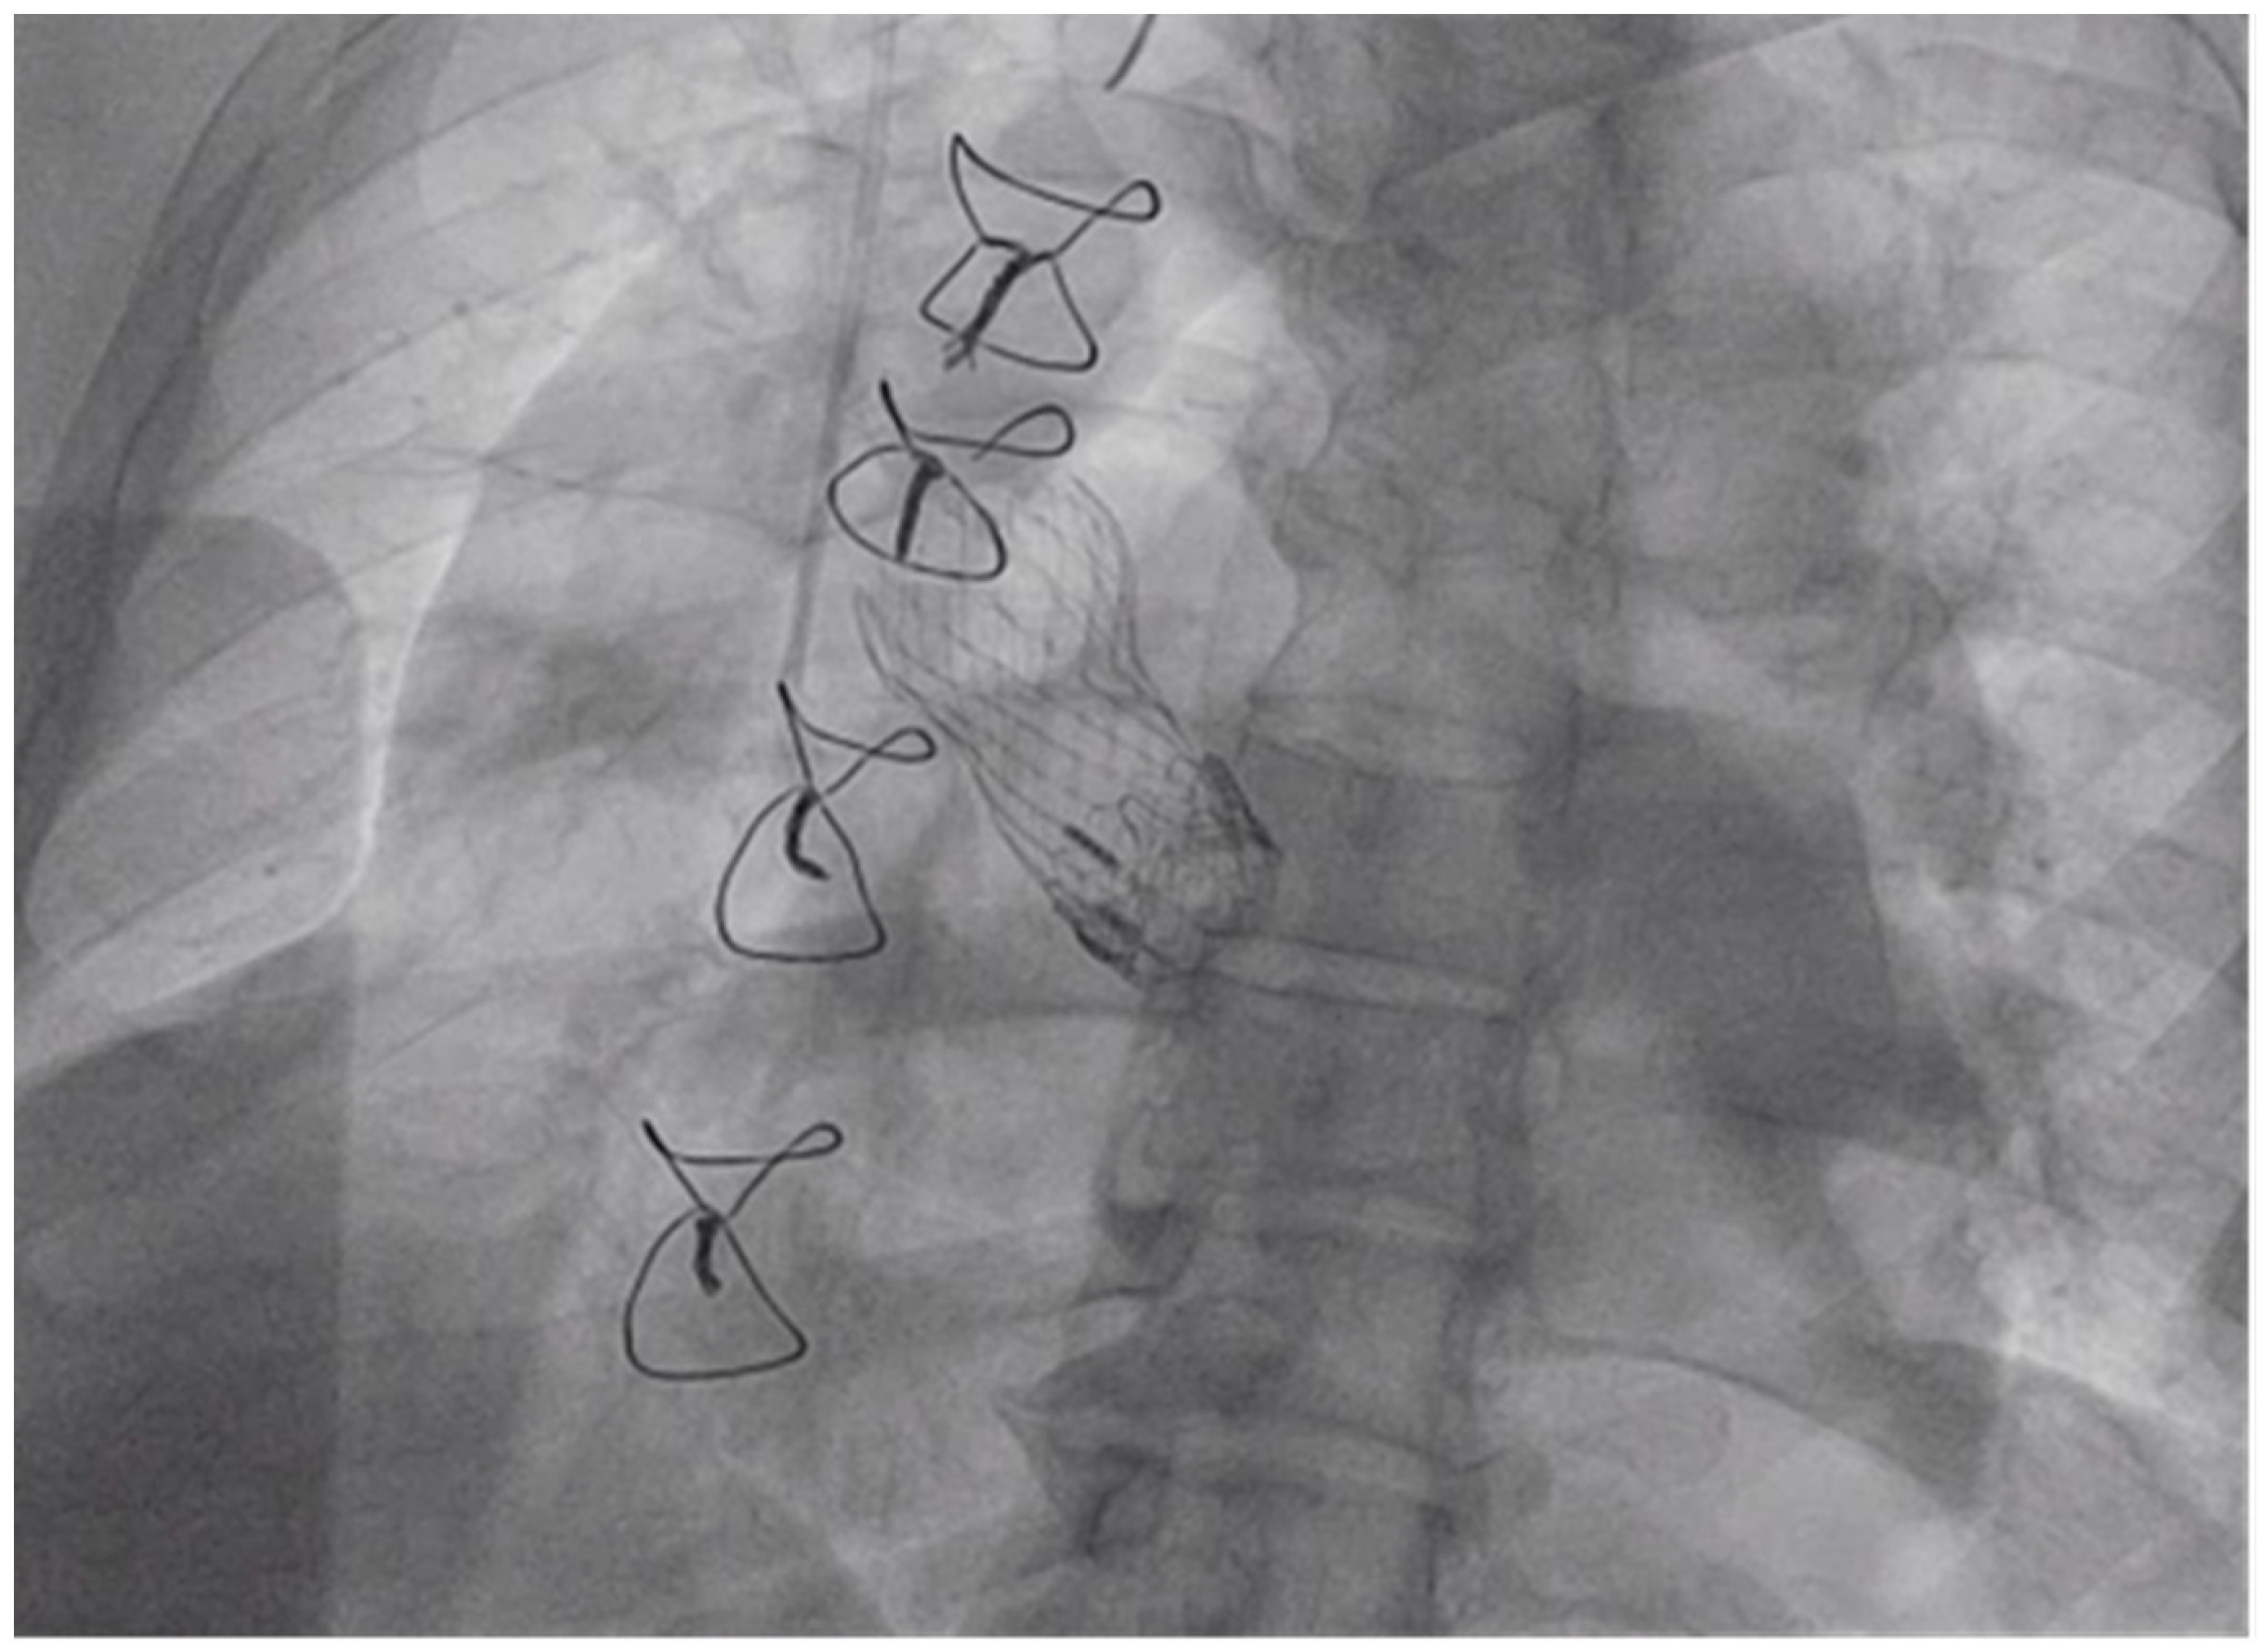

Tandem Life® support was increased to 4 L per minute. At this point, the Gore dry seal sheath was removed from the right femoral artery, and the 26 mm Medtronic CoreValve EvolutR valve delivery system was introduced via the right femoral artery via its in-line sheath, advanced into position across the valves as shown in Figure 4, and deployed in standard fashion with right ventricular pacing at 100 beats per minute.

Figure 4.

Left Anterior Oblique (LAO) Caudal View: Valve being deployed while transvenous pacemaker in place.